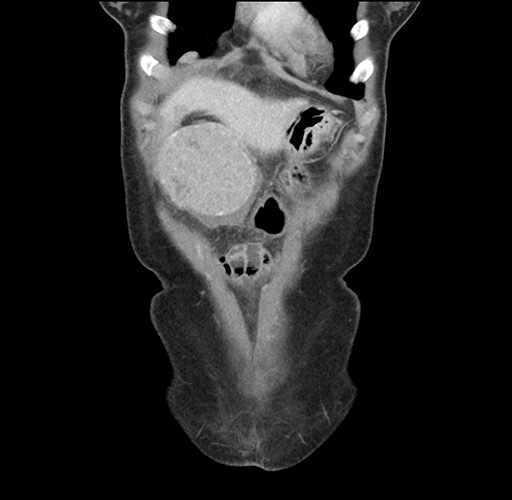

Imaging Analysis

Look through the patient's CT scan to identify any areas of concern for the necessary procedure.

Based on your CT findings, which issue(s) would give reason for "planned slowing down moment(s)" in this case?

Considering a standard left lateral sectionectomy procedure, what step(s) of the operation would you do differently in this case ?